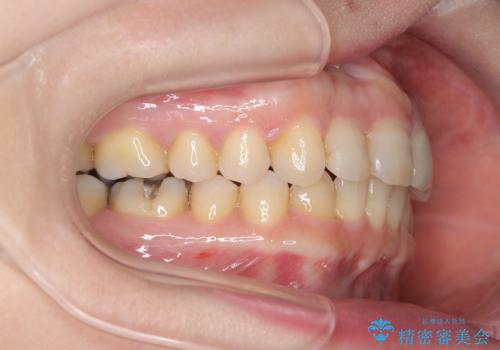

八重歯と口元のバランスを整えた矯正治療

- 「八重歯をきれいにしたい」とのご希望で来院されました。診察の結果、上顎犬歯の萌出スペースが不足しており、典型的な八重歯(叢生)の状態でした。上下の歯の中心(正中)のずれや、奥歯のかみ合わせ(臼歯関係)のアンバランスも見られたため、単に見た目を整えるだけでなく、全体的な機能改善も必要と診断しました。

治療中は咬合バランスや歯列の中心(正中)の位置にも注意を払い、最終的には上下の正中が一致し、左右の臼歯関係も理想的な形に改善されました。見た目の変化はもちろん、かみ合わせの安定や清掃のしやすさも向上。

患者さんからは「笑ったときの印象が大きく変わって嬉しい」「しっかり噛めるようになった」との感想をいただきました。現在は保定装置で後戻りを防ぎながら、良好な状態を維持しています。